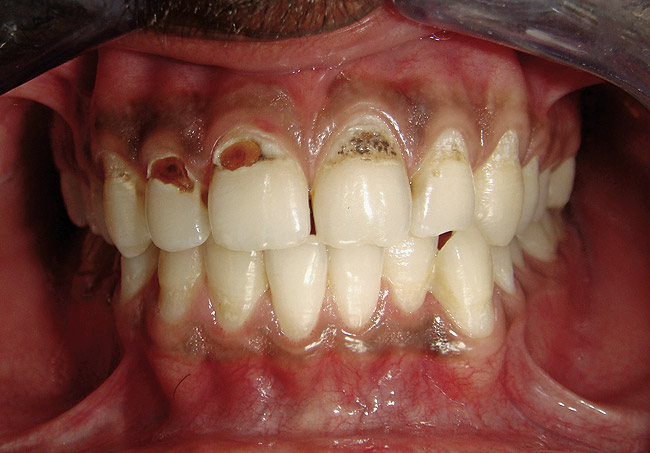

Figure 2  Caries extending cervically on upper right incisors.

Figure 2

Figure 3  Placement of rubber dam with application of cervical clamp on central incisor for extra retraction.

Figure 3

Figure 4  Final composite restorations with respect to upper right incisors.

Figure 4